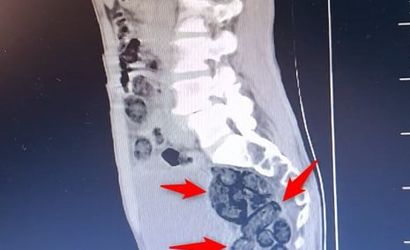

Aramada durumundan şüphelenilen yabancı uyruklu bir yolcu üzerinde yapılan incelemede, şahsın midesinde 64 parça halinde toplam 472 gram metamfetamin bulunduğu tespit edildi.

Bulunan uyuşturucu, sağlık ekiplerince şahsın midesinden çıkartıldı. Emniyetteki işlemlerinin ardından adliyeye sevk edilen şahıs, çıkarıldığı mahkemece tutuklanarak cezaevine gönderildi.